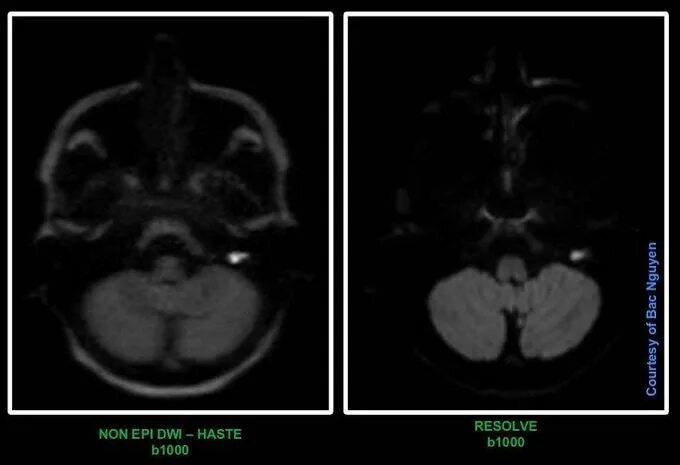

Мрт височных костей в режиме dwi